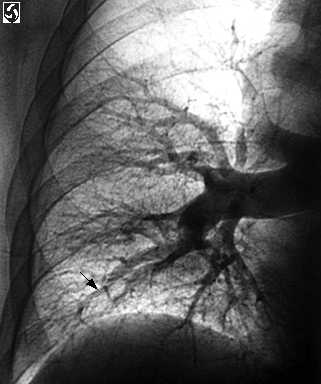

Selectivo derecho pulmonar angiogram

Pulmonar angiography da a conocer una oclusi�n y terminaci�n brusca ( flecha) de la sucursal subir de la arteria pulmonar derecho, el truncus anterior. El relleno de de fallas ( la flecha) est�n presente dentro de las arterias que abastecen los basal segmentos del l�bulo m�s inferior derecho.

La ingle derecho de paciente estuvo dispuesto y tapiz� usando t�cnica est�ril. El Seldinger de t�cnica se us� a percutaneously punzada la derecho com�n femoral la vena con un 18 indicador separa - tapiada de aguja. Un 7 Franc�s pigtail catheter se puso en el inferior vena cava sobre un J-guide el est�ndard cable. El cable se quit�. Un yodo alto (350 mg/ml) nonionic contrasta de medio se infundi� en el catheter y un inferior venacavagram mostrado que el cava estuvo sin thrombus. El catheter se dirigi� mediante el atrio derecho, ventr�culo derecho, extensi�n pulmonar de efusi�n, y arteria pulmonar principal. Las grabaciones de presi�n dadas a conocer una levemente elev� la presi�n principal de arteria pulmonar (37/15 mmHg, significa de 17 mmHg). La presi�n normal de arteria pulmonar era 20-25/8-12 con una significada presi�n de 15. Desde este paciente V/Q repasa mostr� pulm�n predominantemente derecho perfusion fallas, la substracci�n digital selectiva angiography del pulm�n derecho se desempe��. Los derecho pulmonar arteriogram los im�genes mostraron cesaci�n brusco del truncus anterior por occlusive thrombus. Hab�a tambi�n intraluminal fallas de relleno dentro de basilar arterias l�bulo a la derecha m�s inferior. Estos hallazgos proveyeron diagn�stico definitivo de PE.